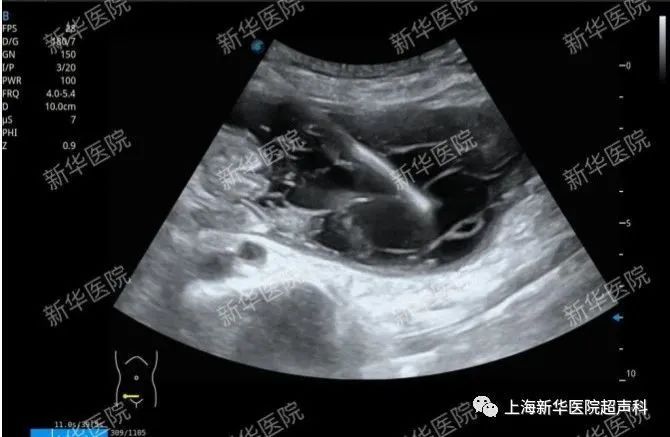

(1)包括胸腔积液、腹腔积液、术区积液、浅表及深部脓肿等疾病的抽吸或置管引流。已置管患者术后随访监测,评估是否可拔管,引流不通畅患者寻找堵塞原因,需长期带管患者可进行穿刺点换药及更换引流袋等。

盆腔脓肿穿刺引流术